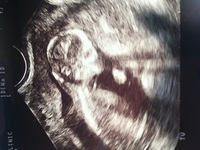

3dエコー写真のおすすめ時期は 早くても妊娠14週から、遅くても32週ごろ と言われています。 赤ちゃんの成長によって見え方が変わってきます。 全身を見たいか、顔の表情だけで十分なのか、病院と相談しつつ時期を決めるのがいいですね。4Dエコーとは、3Dエコーに赤ちゃんの動きを加えたもので、お腹の中で動いている赤ちゃんの様子をリアルタイムで見ることができ、赤ちゃんの様子をよりわかりやすく視覚化できます。 当院で妊婦検診中の方は14週頃から毎回健診時に3D4Dを見ることができます。 健診では短時間のため、ゆっくり見たい方という方はご予約下さい。 他院で妊婦検診中の方もご予約 エコー検査によって妊娠11週目でダウン症であるという診断がつけられるのか? という疑問を持つ妊婦さんもいるようです。 一般にダウン症はエコー検査ではわからないし、 診断しようとするべきではないとも言われます。

エコー検査とは? エコー検査とは妊娠週数に応じて、赤ちゃんが元気がどうか、成長過程に正常から逸脱したところがないかを確認するために行う、超音波検査をさします。 現在、よく使われているのが2D(Two Dimensional)の平面的なエコー検査で、妊娠初期には膣に器械を入れて検査(経膣法)が行われ、妊娠の中期には経腹法といって妊婦さんのお腹に器械を当て妊娠週 14w0d 悪阻も治まりつつある中での検診。 この日は寝てたのかあまり動いてはいませんでした。 しかも背中を向けて、左手を耳の辺りに当てていて顔が見えませんでした(;_;)一緒に見ていた娘も顔が見えなかったので微妙な反応(笑)赤ちゃんの大きさは84cmで、順調でした。 おなまえ えりもんち ねんれい 30 妊娠週 14w0d BPD273cm このあと4Dに切り替え妊娠11週のエコー写真は? おなかの大きさは? 妊娠11週を迎えると胎児の手足が伸びてきて、超音波検査のモニターに映る姿は人間らしくなります! おなかの中で胎児が確実に育っていると実感できるこのころ。

妊娠14週目 胎児の大きさ・体重・エコー写真 妊娠14週(14w)になると、胎盤も完成に近づいてきます。 赤ちゃんは首が発達してきて長くなり、あごが胸にくっついていることがなくなってきました。 また腕と体の比率が出生時の比率にかなり近づいてきています。 まだ脂肪はついてはいませんが、少しずつ皮膚の厚みが増してき、うっすらとうぶ毛が生えてきてい 14週 エコー 顔 妊娠14週目は妊娠4ヶ月にあたり、妊娠期間の3分の1が過ぎて体調が落ち着いてくる頃です。つわりも落ち着き、ついつい食べすぎてしまうなんてことも。体調管理には注意が必要ですね。そうちゃん成長記録〜ダウン症ボーイ〜 ダウン症の男の子のママです♪ ゆっくりながらも日々の成長を嬉しく楽しく毎日を過ごしています♡ 先輩ママさん、共通点の多いママさんからのコメントとても嬉しいです! よろしくお願いします \( °∀° )/